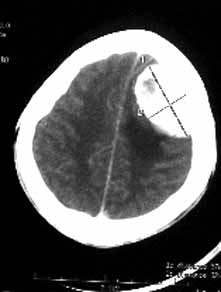

男性,36岁,头痛数年,近期伴有视蒙。

ct诊断:左额颞部脑膜瘤。